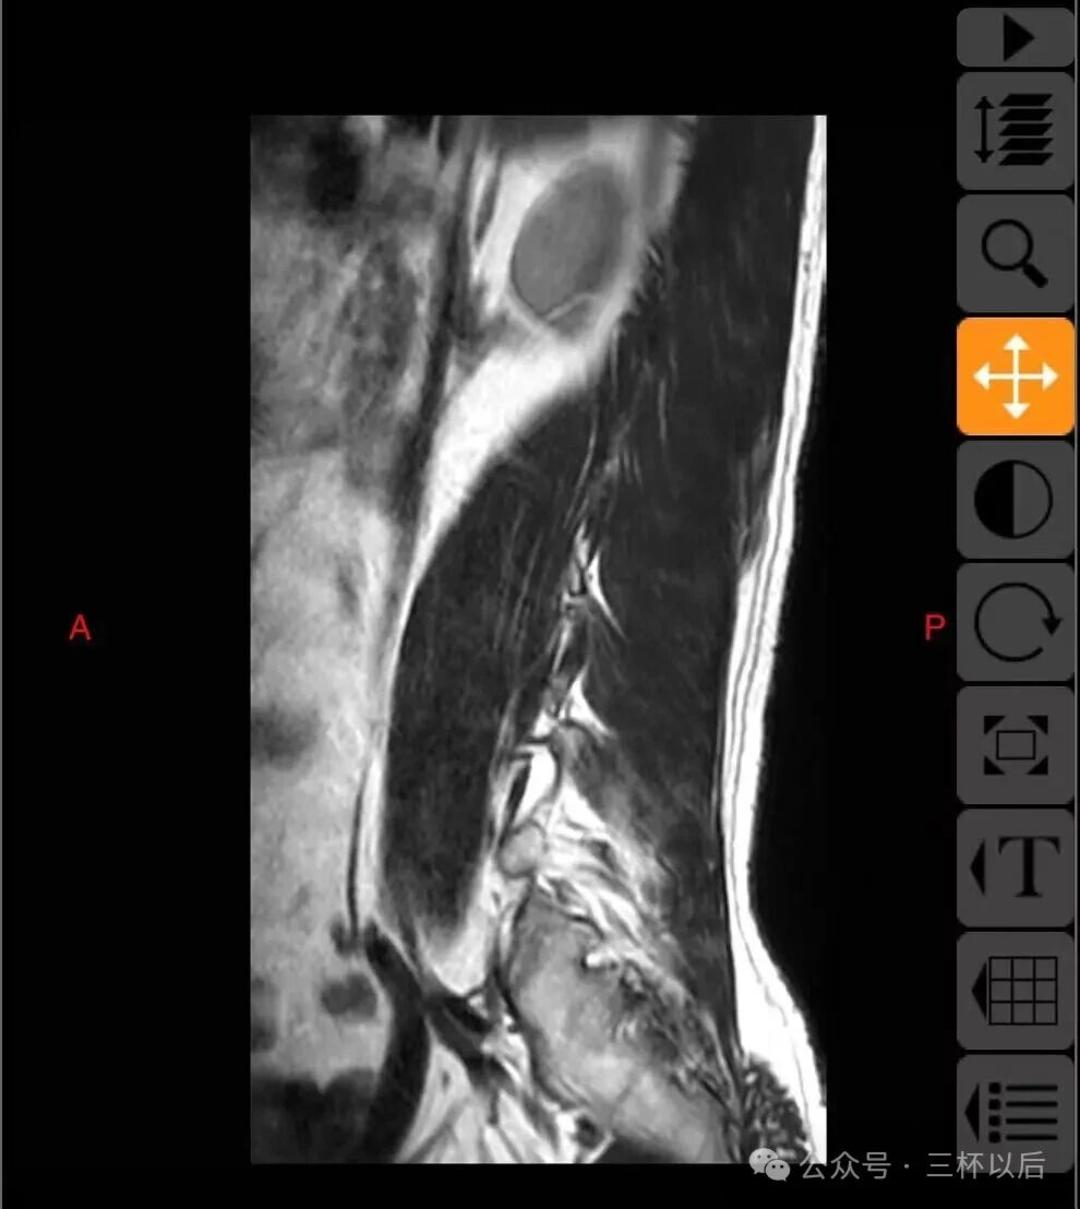

顺便贴一下拍的片子,如果有懂行的欢迎给我建议,我听劝的。真真希望能恢复如初,现在每天都能感受到疼痛,用了各种办法也不管用。